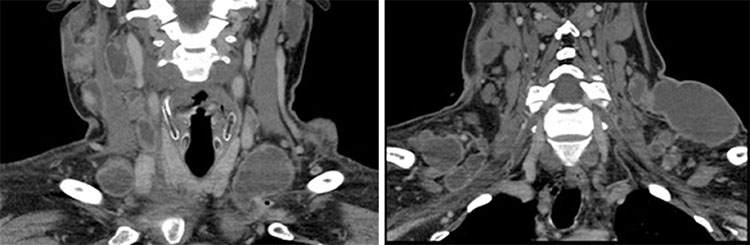

Después del compromiso pleural, es una de las localizaciones más comunes de la TBC extrapulmonar, la presentación cervical o supraclavicular es el grupo ganglionar más comúnmente afectado.7 El compromiso de adenopatías cervicales que se puede apreciar al examen físico, recibe el nombre de adenitis cervical tuberculosa o escrofulosis (Fig. 1).

Hombre con tumefacción no dolorosa en el cuello, mostró fiebre, diaforesis y baja de peso. Se realizó tomografía computada (TC) de región cervical, destacándose múltiples adenopatías con compromiso ganglionar con realce periférico y atenuación hipodensa central. Se realizó diagnóstico de adenitis cervical tuberculosa o escrofulosis.

En TC, se aprecian linfonodos con un engrosamiento periférico y una atenuación hipodensa central (Figs. 1 y 2). Esas imágenes son muy sugerentes de una TBC ganglionar, pero no es patognomónico, por lo que se debe tener en consideración diagnósticos diferenciales como metástasis, linfoma y patologías inflamatorias.8